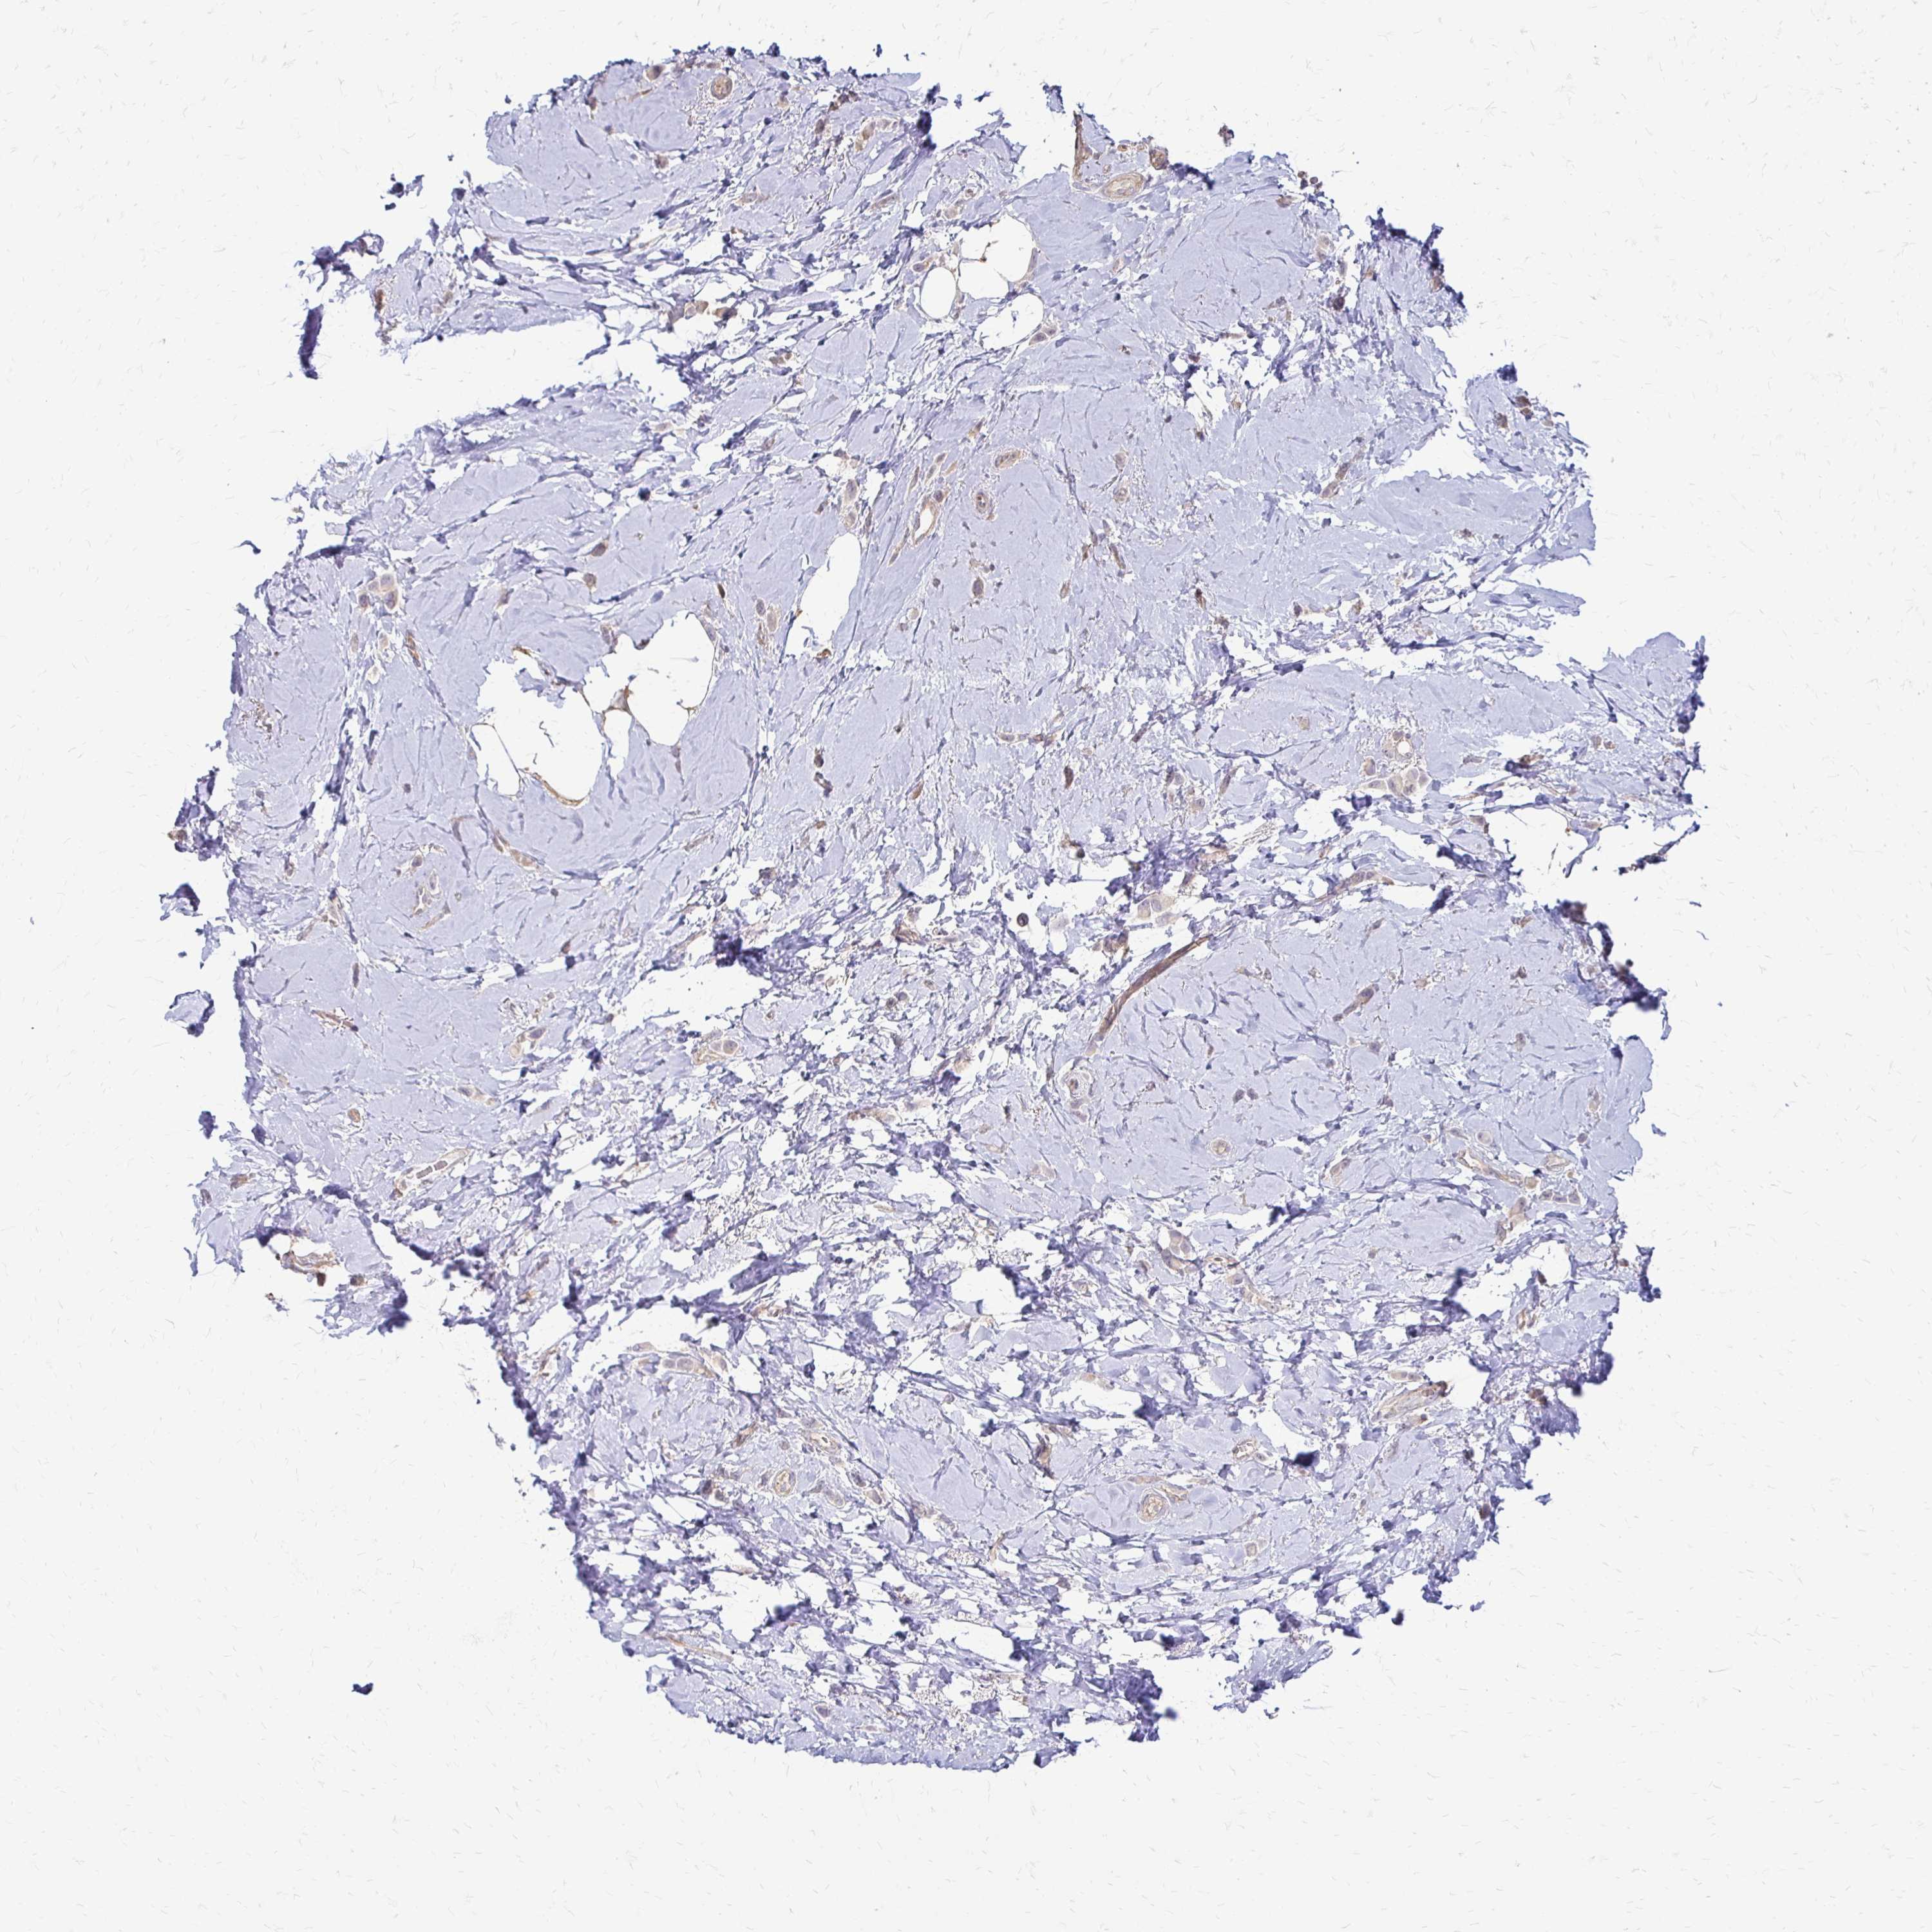

BRCA TCGA BRCA VALIDATION PROTEIN EXPRESSION

ANTIBODIES

AND

VALIDATION